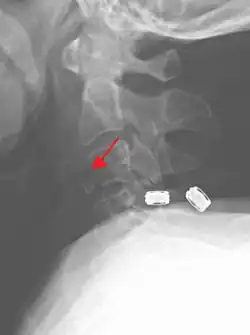

On CT scan or X-ray, a cervical fracture may be directly visualized. In addition, indirect signs of injury by the vertebral column are incongruities of the vertebral lines,[7] and/or increased thickness of the prevertebral space:[8]

X-ray of normal congruous vertebral lines -